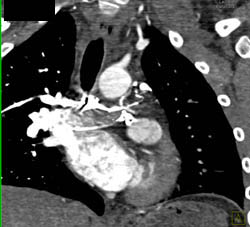

Huge Pericardial Effusion in Lymphoma Patient